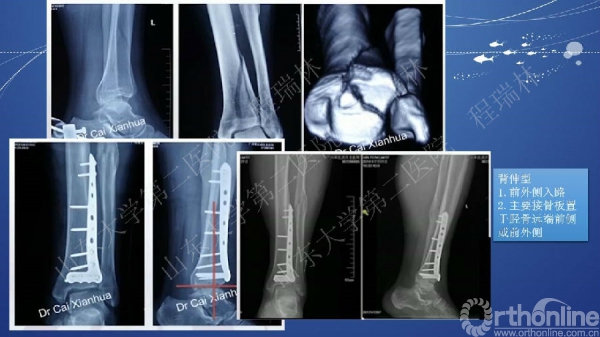

Pilon骨折的手术基本原则

Pilon骨折是踝部的复杂骨折,以高能量损伤、不稳定、软组织损伤严重为特点。手术复杂,并发症常见且严重。一旦治疗失败,常常带来灾难性的后果,如截肢、严重创伤性关节炎后期再关节融合等。

Pilon骨折的治疗目的:软组织保护,恢复下肢力线,解剖复位关节面。